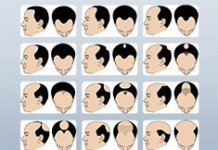

У вас лысый муж? Он может умереть от инфаркта

У вашего мужа есть лысина на макушке? Будьте внимательны, американские ученые доказали, что это связано с высоким риском развития ишемической болезни сердца и ранней...